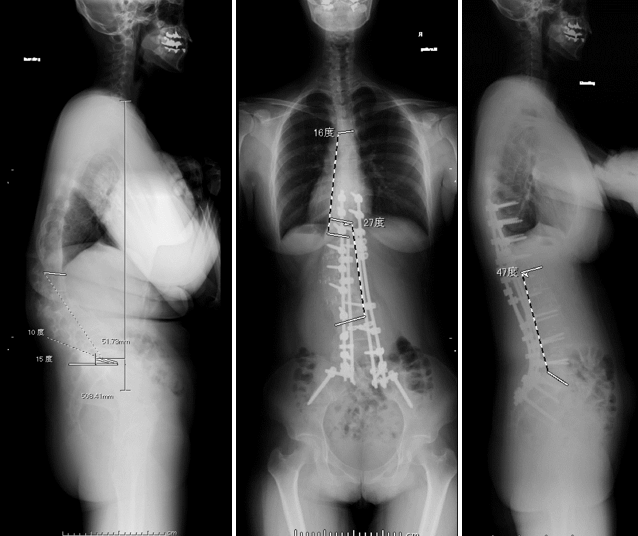

第14回 側弯症の矯正固定術脊椎手術.com。

側弯症の治療の実例脊柱側弯症 側湾症 柳沢療法研究所。